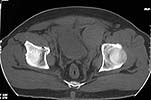

Here are the post op pictures.

To recap: Middle aged male patient on whom a heavy log fell and sustained injury. Had pelvic ring disruption with fracture femur. Ext fix of pelvis and interlocking nailing of femur done. Developed compartment syndrome thigh and had fasciotomy. Went on to rhabdomyolysis and ARDS. Managed with ventillation and alkalinising. Fasciotomy wound later skin grafted.